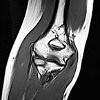

MRI of the elbow joint.

Магнитный резонанс локтевого сустава. Это метод исследования, позволяющий визуализировать сухожильно-связочный аппарат, регионарные нервные и сосудистые структуры, дистальные части плечевой и проксимальной частей локтевой и лучевой костей, а также суставную полость. С помощью этой процедуры можно выявить дегенеративно-дистрофические и воспалительные изменения в суставных поверхностях костей, разрыв структуры суставной полости, наличие опухолей, травматические повреждения - разрывы связок, искажение сухожилий, вывихов, переломов и переломов, наличие отломков, гематомы и гемартроз. Обычно магнитный резонанс локтевого сустава используется в качестве дополнительного метода для неоднозначных результатов других исследований: рентгенография, УЗИ, КТ Как правило, эта процедура не требует специальной подготовки.